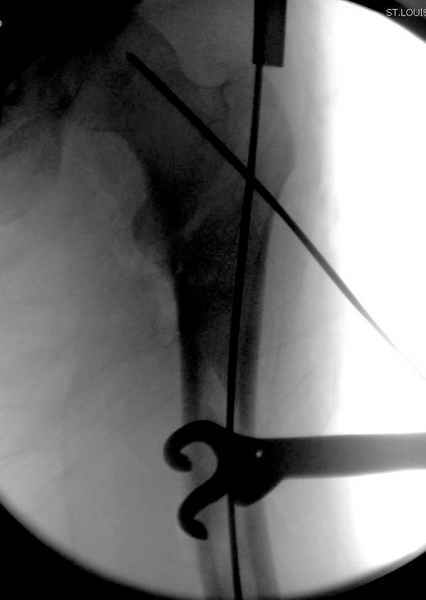

Как раз недавно у меня был примерный случай: больному 36 лет, поступил ночью, травма в результате мотоциклетной аварии, кроме чрезвертельного и спирального перелома левого бедра имеется переломы костей предплечья с этой же стороны. Скелетное вытяжение, а на следующий день больной про оперирован на ортопедическом столе с дистракцией. Чтобы не расколоть чрезвертельный перелом провели временную спицу ближе к переднему кортексу, из малого разреза костодержатель для репозиции, а фиксацию провели антиградным штифтом. Этапы операции на снимках.